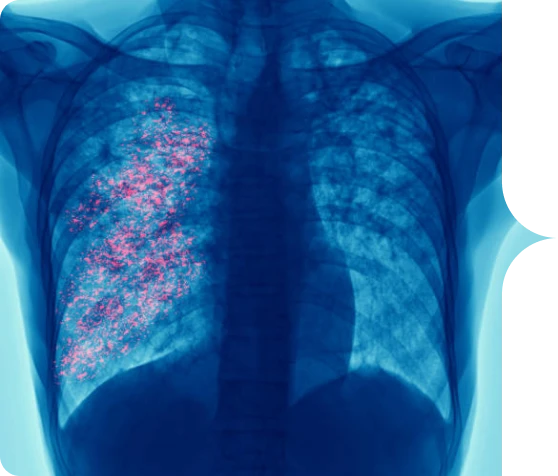

Virus Sincicial Respiratorio o VSR

es un virus frecuente que infecta la nariz, la garganta, los pulmones y que generalmente causa síntomas leves

y similares a los de un resfriado.1,2

Algunas personas, especialmente los adultos mayores y los bebés menores de 6 meses, pueden necesitar hospitalización. El VSR puede causar bronquitis (inflamación de las vías respiratorias pequeñas en el pulmón) y neumonía (infección en los pulmones).1,2